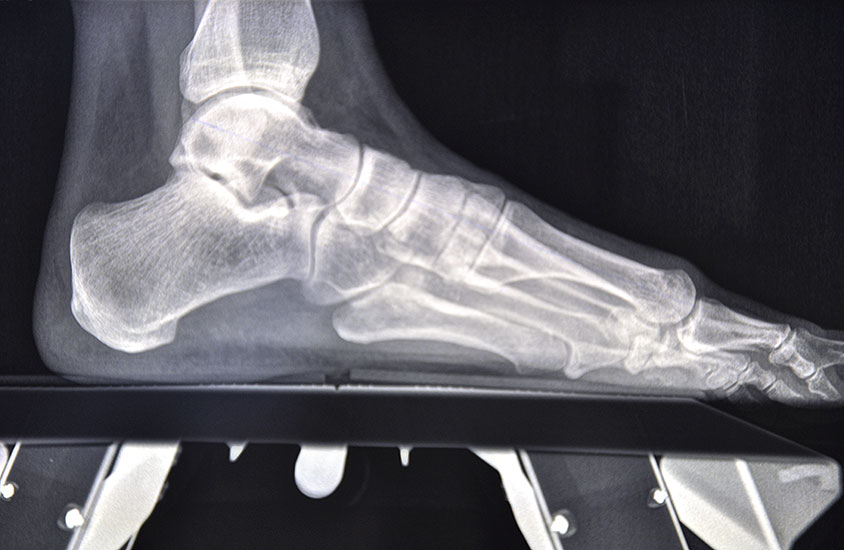

Die primäre Therapie von belastungsabhängigen Beschwerden im Vorfußbereich ist konservativ. Im Rahmen der Diagnostik werden Röntgenbilder des ganzen Fußes im Stehen angefertigt, um die statischen und funktionellen Verhältnisse des Vor- und Rückfußes zu beurteilen.

• Klinische Untersuchung, Anamnese, Bildgebung mit Röntgen des Fußes unter Belastung in mindestens 2 Ebenen.